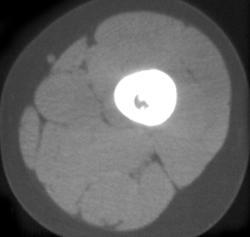

Transverse Process Fracture With Hematoma